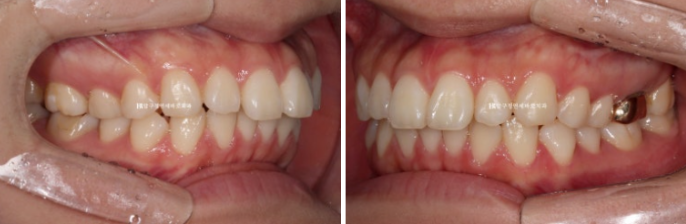

23.06

Because the front tooth protrusion was severe, the treatment plan was set as extraction orthodontics with removal of the two upper premolars, and treatment began.

At the initial examination, it was expected that if the lower lip were pulled back too much, the appearance would not be good, so for the lower arch the plan was to remove the impacted wisdom teeth without extracting the premolars, place mini-screws, and move the teeth back slightly.

Clippy-C orthodontics was chosen.